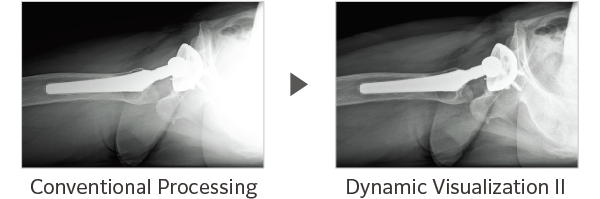

Dynamic Visualization II

Optimizes image quality using latest Exposure Data Recognizer

Advanced recognition algorithms using automatic  calculations of estimated 3D image data, identify the body part required and adjusts contrast, density and enhancement for optimised image display. (Option)

Comparison of Dynamic Visualization II vs. conventional processing images (Lumbar Spine)

Comparison of Dynamic Visualization II vs. conventional processing images (Hip Joint)